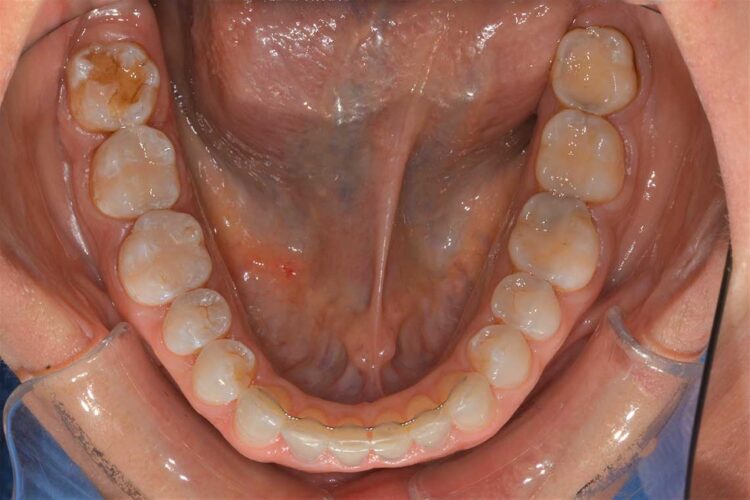

Ortodonzia allineatori – caso clinico 2